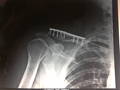

Visita a EcoXtreme [20120227] - Fractura de Clavícula

Me operaron el 1 de marzo y me pusieron una placa de titanio de 15 cm y tornillería variada (rectos y expansores).

Así quedó mi clavícula derecha luego de una bajada

áspera en el EcoXtreme el día lunes 27 de Febrero

de 2012 (http://www.btt.com.ar/foro/viewtopic.php?

f=22&t=1993&start=150#p9881).